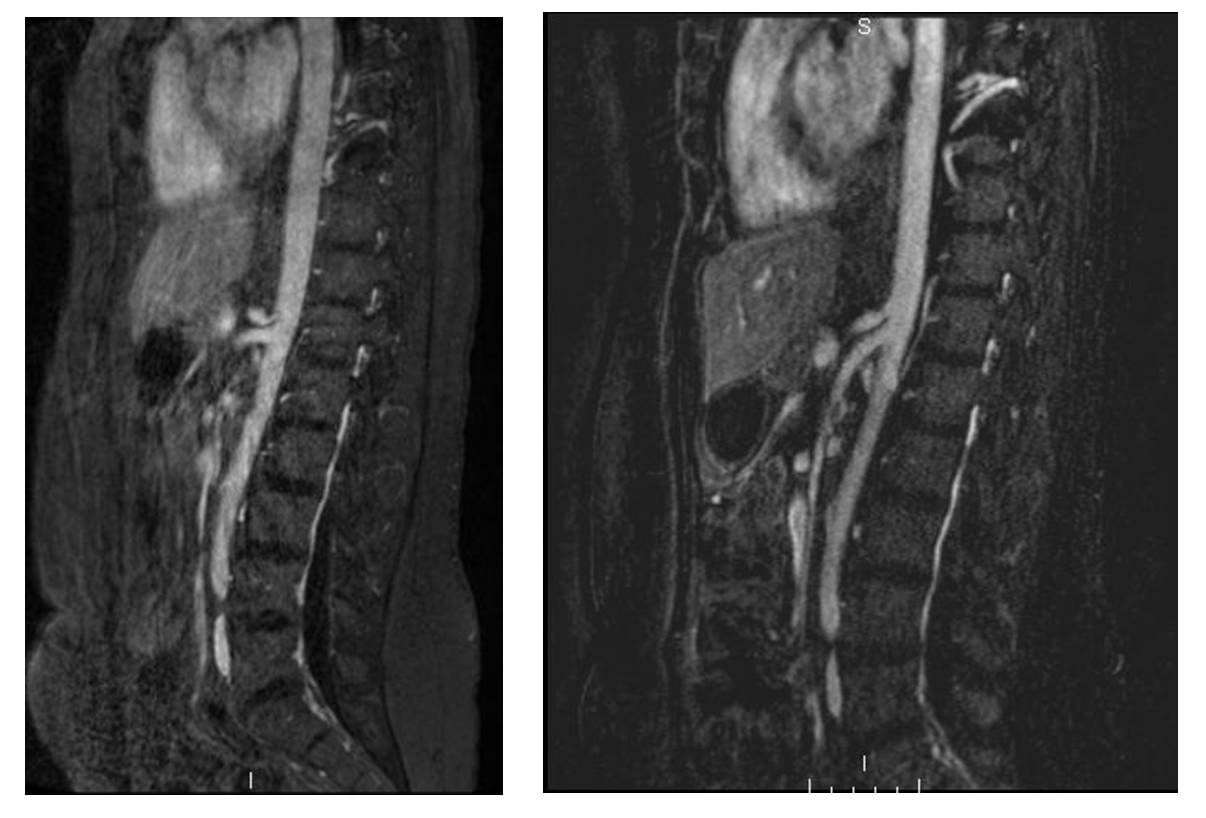

- Magnetic Resonance Angiography – MRA with a contrast agent that has a long-lasting half life, such as Ablavar. Thus respiratory maneuvers can be replicated with the MRA. An advantage of MRA over ultrasound is that it offers more information about atherosclerosis in other locations.